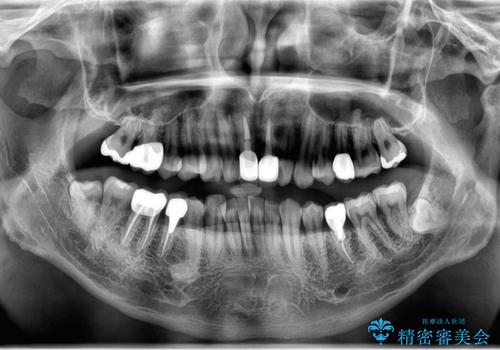

- 銀歯をすべてやり替えたいとのことで来院された患者様です。

再根管治療が必要なところは再根管治療から、そうでないところは補綴物のみをやり替えていくこととなりました。

銀歯のやり替えと並行してホワイトニングも行いました。

結果的には銀歯がすべて白くなり、前歯のガタつきもある程度改善され大変喜んでいただけました。

治療終了時からナイトガードを使用していただき、歯ぎしりによる破折を予防しています。